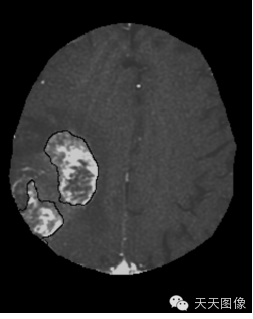

下面只上几张比较中规中矩的肿瘤图像。

上面是一些典型的脑肿瘤图,图中的白块就是肿瘤。为了让大家看的更直观,特地选出来一些比较好分割的图像,但是也并不是什么方法都能分割出来的,就我个人知识而言,不进行任何预处理,没有一种方法可以自动地直接将这些肿瘤都给分割出来。不信可以去问问周边搞图像的人,如果有,请务必告诉我。

下面是我的分割结果,算不上完全自动,但是也是基本上不需要监督。(仔细看肿瘤周围叠加的轮廓,就是分割的结果)

用到的方法就是水平集。